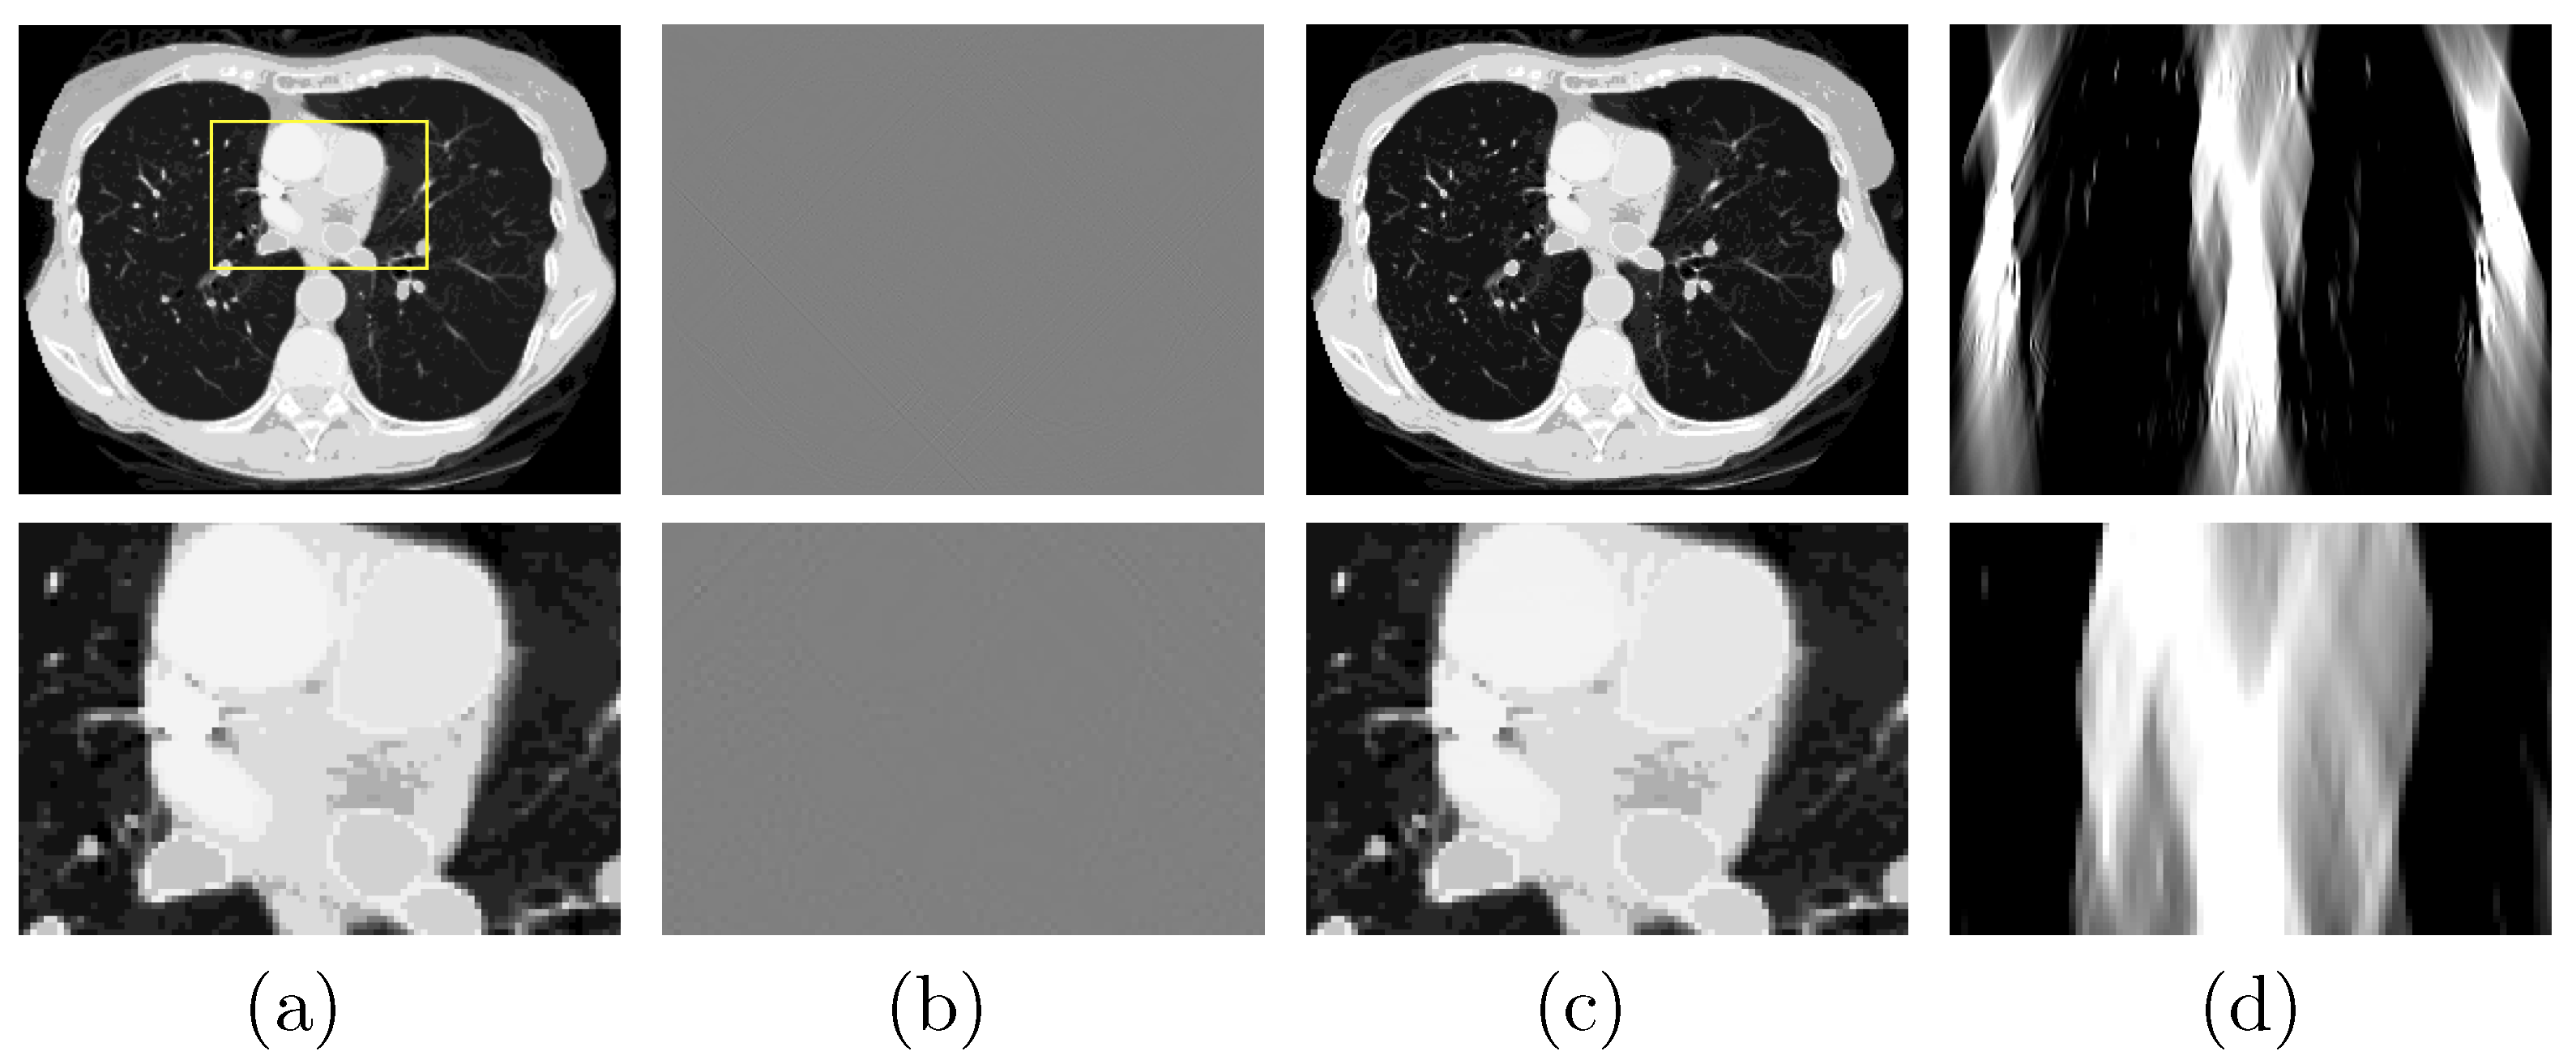

3.2.1. Verification Study with the Chest Phantom